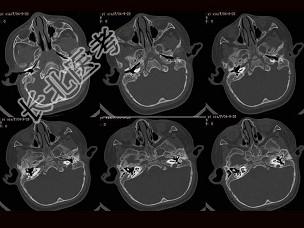

- 单项选择题女,2岁, 两侧耳廓发育不对称,左侧听力差, 如图所示,最可能的诊断为 ( )

A、左侧外耳道闭锁

B、左侧中耳炎

C、左侧内耳道畸形

D、左侧胆脂瘤

E、左侧中耳炎胆脂瘤形成